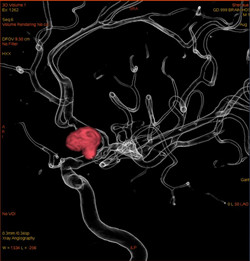

【优势一】智能3D引导,无失真3D脑血管影像,三维指引栓塞。

脑动脉瘤是导致脑出血的重要原因之一,一旦破裂应及时治疗,介入治疗是主要方法之一。一般体积增大、形态改变建议手术;未破裂动脉瘤导致心理障碍,影响工作生活的可考虑手术。脑动脉瘤介入治疗就是把一个很细的管放入动脉瘤内,然后通过这个导管往里面填塞非常柔软的金属弹簧圈,将动脉瘤完全堵塞防治再次破裂或生长。

▲经过造影剂显影,脑血管变得清晰可见。

双侧颈内动脉3D重建技术,显示的是人两侧大脑半球动脉血管图像。

▲脑血管造影检查发现脑动脉瘤。

血管影像透明化技术让动脉结构一览无遗,更精准引导动脉瘤治疗。